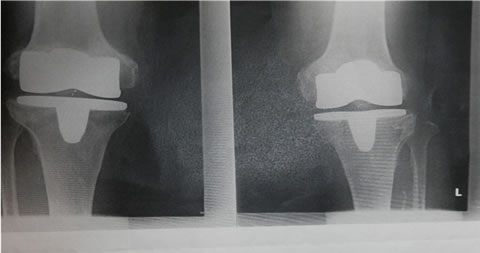

私の人口膝関節

←白いのが金属で、ここに映っていませんが、

この間に厚さ1cmほどの円筒状の特殊ポリエチレン製の

軟骨に相当するものが挿入されています。 |